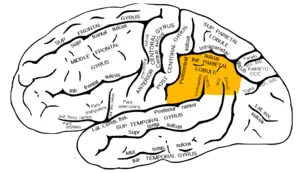

| The inferior parietal lobule, with damage in this area most often associated with Gerstmann syndrome | |

Gerstmann syndrome is a neuropsychological disorder that is characterized by a constellation of symptoms that suggests the presence of a lesion usually near the junction of the temporal and parietal lobes at or near the angular gyrus. Gerstmann syndrome is typically associated with damage to the inferior parietal lobule of the dominant hemisphere. It is classically considered a left-hemisphere disorder, although right-hemisphere damage has also been associated with components of the syndrome.[1]

This disorder is often associated with brain lesions in the dominant (usually left) hemisphere including the angular and supramarginal gyri (Brodmann area 39 and 40 respectively) near the temporal and parietal lobe junction. There is significant debate in the scientific literature as to whether Gerstmann syndrome truly represents a unified, theoretically motivated syndrome. Thus its diagnostic utility has been questioned by neurologists and neuropsychologists alike. The angular gyrus is generally involved in translating visual patterns of letters and words into meaningful information, such as is done while reading.